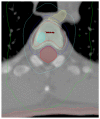

Materials/methods: Seventeen men with 21 PCa lesions were treated with SBRT between February 2009 and November 2011. All patients had a detectable prostate-specific antigen (PSA) at the time of SBRT, and 11 patients (65%) had hormone-refractory (HR) disease. Treatment sites included bone (n = 19), lymph nodes (n = 1), and liver (n = 1). For patients with bone lesions, the median dose was 20 Gy (range, 8-24 Gy) in a single fraction (range, 1-3). All but two patients received some form of anti-androgen therapy after completing SBRT.